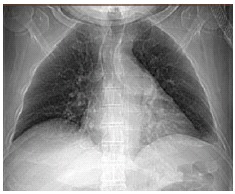

神经痛性肌萎缩症(NA)是一种罕见的、急性发作的炎症性臂丛病,通常表现为急性疼痛,然后是肩带肌无力。膈神经受累影响膈发生在7-10%的病例。我们报告一名52岁男性,患有神经性肌萎缩伴膈神经受累和双侧膈肌麻痹,伴有明显的呼吸症状和睡眠低通气,采用无创通气和容量保证压力支持模式治疗。发病21个月后,患者在骨科、睡眠质量和功能状态方面均有明显改善。这是首次报道的使用这种无创通气模式治疗神经性肌萎缩症的病例。

Neuralgic Amyotrophy (NA) is a rare, acute onset inflammatory brachial plexopathy that frequently presents with acute pain followed by shoulder girdle muscle weakness. Phrenic nerve involvement affecting the diaphragms occurs in 7-10% of cases. We present the case of a 52-year-old man with neuralgic amyotrophy with phrenic nerve involvement and bilateral diaphragmatic paralysis with marked respiratory symptoms and sleep hypoventilation, who was treated with non-invasive ventilation with volume assured pressure support mode. By 21 months post disease onset, the patient had experienced marked improvement in orthopnea, sleep quality and functional status. This is the first reported case of the use of this mode of noninvasive ventilation in neuralgic amyotrophy.